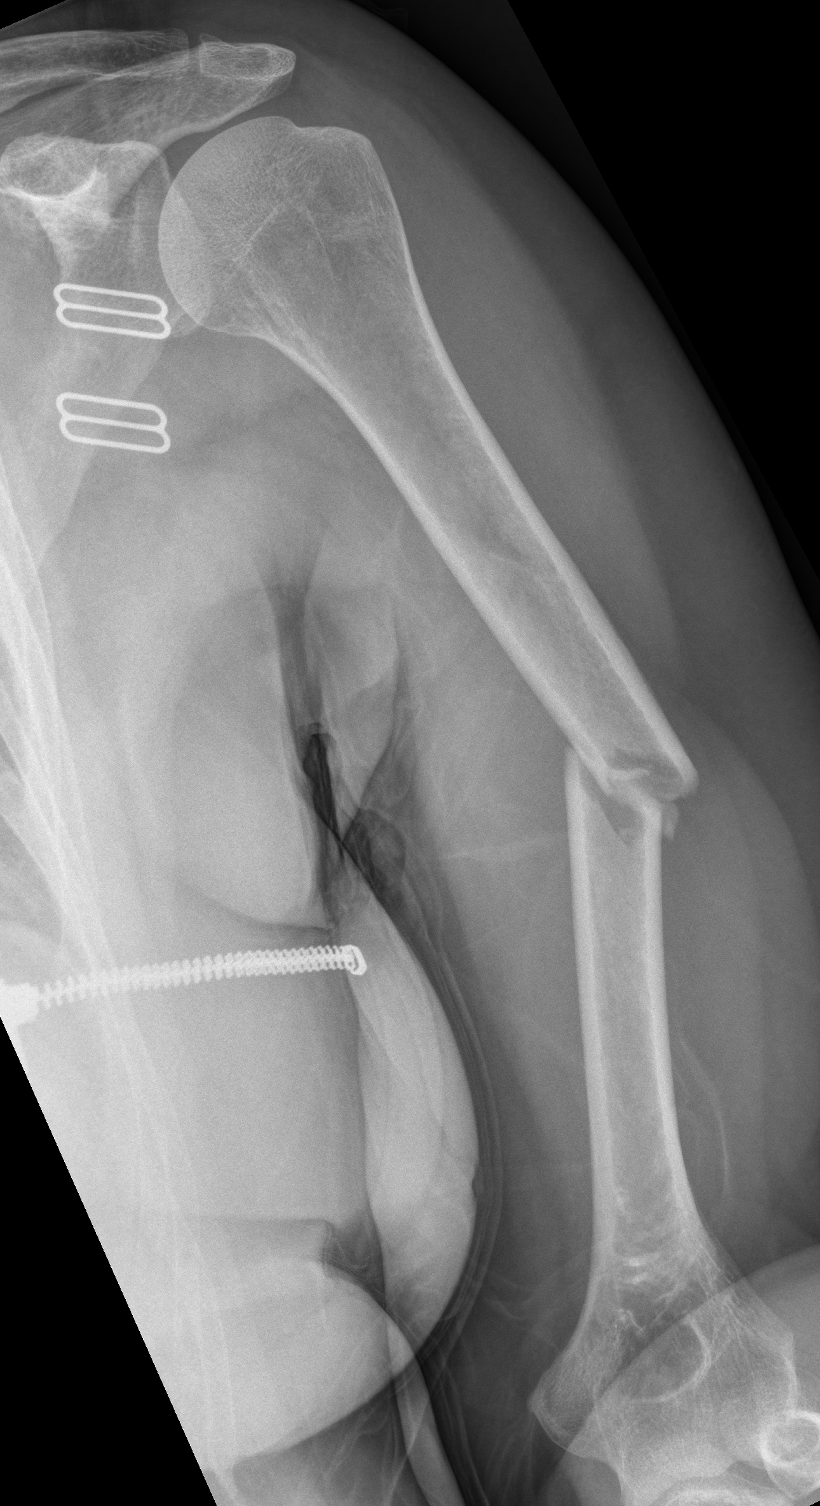

Fracture de la diaphyse humerale

Henry Knipe, Radiopaedia.org. From the case rID: 31234